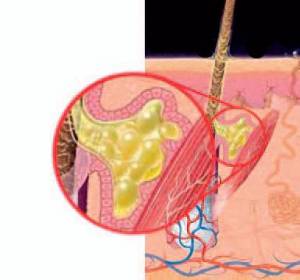

Gruczoły łojowe to bardzo ważne struktury budowy naszej skóry, biorące udział w wielu, zarówno biernych, jak i aktywnych jej funkcjach.

Gruczoły łojowe to bardzo ważne struktury budowy naszej skóry, biorące udział w wielu, zarówno biernych, jak i aktywnych jej funkcjach.